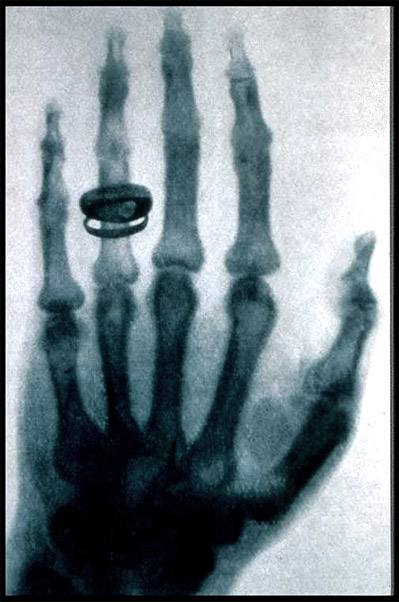

X射线是著名的伦琴发现的,它是影响医学的开端。X线发明的故事大家也都熟悉,伦琴在一个偶然的机会下从X射线现中看见了自己手的骨骼。所以说X射线主要是用来看骨头。

此外还有一个最常见的作用是拍胸片,主要是粗略的看一下肺部和心脏的轮廓。一些诸如肺部感染,先天性心脏病导致心脏的大小形态变化,还有肺癌之类的典型的影像表现还是可以一目了然。还有人问什么透视和拍片有什么区别。简单的说透视就是医生在X光下看一眼,拍片就是把片子打印出来。